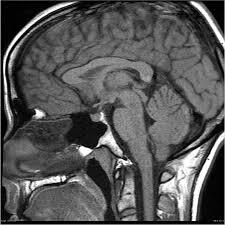

Are you looking for an affordable MRI of the Pituitary Gland? At Medifyhome, we offer competitively priced MRI scans, partnering with top NABL-certified diagnostic centres and clinics. Our facilities ensure high-quality imaging and accurate results. An MRI of the pituitary gland is a specialised imaging technique used to visualise this small, pea-sized gland located at the base of the brain. The pituitary gland plays a crucial role in hormone regulation and overall endocrine function. MRI is preferred for its ability to provide detailed images of soft tissues, helping to identify abnormalities such as tumours, cysts, or other pathologies. The non-invasive procedure typically requires the patient to lie still within a magnetic resonance machine for about 30 to 60 minutes. Results from the MRI can guide further treatment or management of hormonal imbalances or other related conditions. To book an appointment for an MRI Pituitary Gland, visit our platform Medifyhome or contact us at +919100907036 or +919100907622 for reasonable prices.

An MRI of the pituitary gland is a medical imaging procedure that uses strong magnets and radio waves to create detailed images of the pituitary gland and its surrounding structures in the brain. This imaging technique is particularly useful for diagnosing conditions such as tumours, cysts, or abnormalities in the gland, which is vital for hormone production and regulation. The MRI is non-invasive and typically involves the patient lying inside a large machine for about 30 to 60 minutes. It provides high-resolution images that help healthcare providers assess the gland’s size, shape, and potential lesions. The results can inform treatment plans for hormonal disorders or other neurological issues.